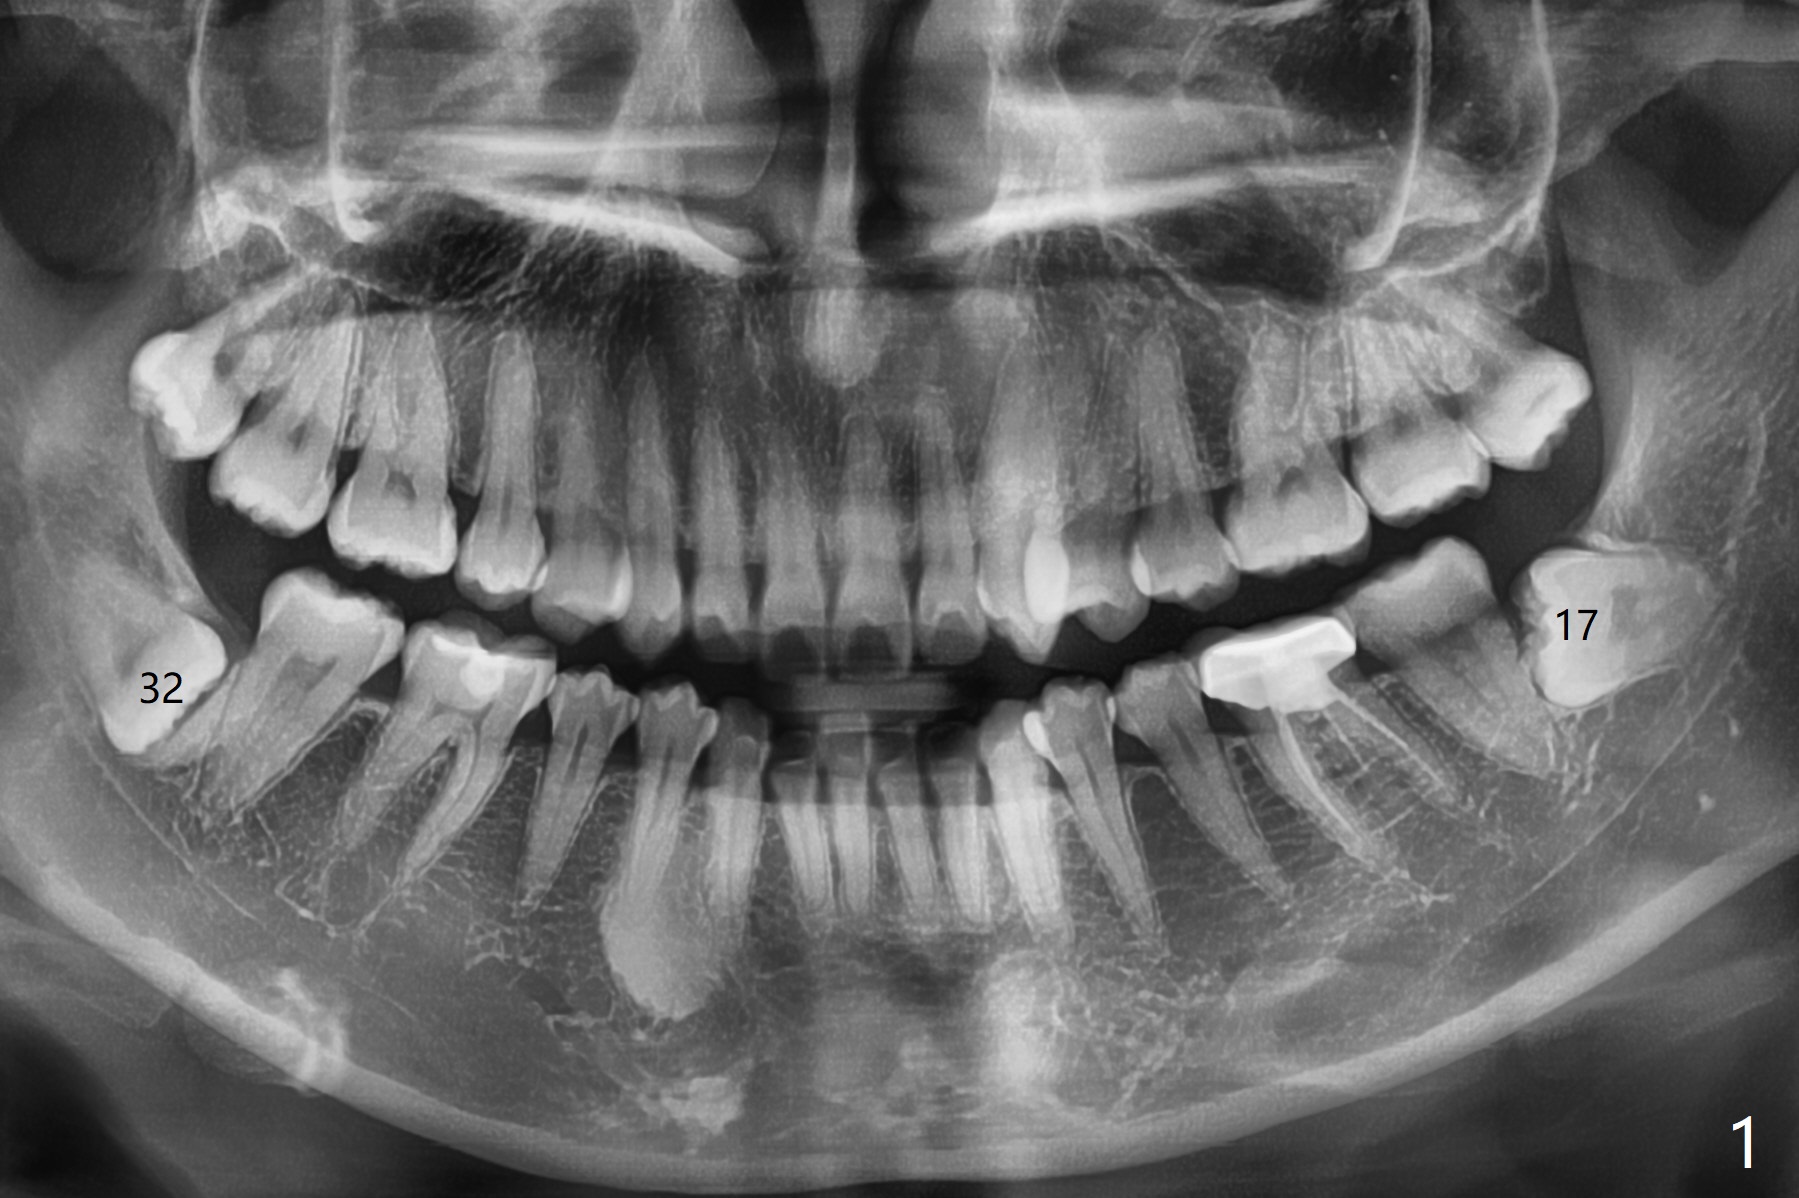

A 31-year-old woman returns with chief complaint of "occasional, mild pain in the lower left 3rd molar" 1 year post extraction of #1 and 16 (Fig.1,2). The lower 2nd molars appears to have a single fused root (Fig.2',2'' S); the radiopaque image mesial to the tooth #32 must be the dense bone (Fig.2' *). In contrast the cortex coronal to the tooth #17 is lacking (Fig.2'' v), as compared to that in Fig.2'. It seems that the bone loss at #17 is associated with mild pericoronitis. The tooth #17 should be extracted with placement of Bond Apatite to repair #18 distal defect. In fact sticky bone and collagen plug are placed instead (Fig.3), covered by 2 pieces of PRF.